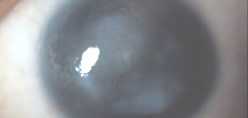

She said the first step, even before treatment, is to stage the disease. She uses live imaging to evaluate the stem cell function in these eyes. “We do anterior segment OCT first to look at the epithelial thickness in these eyes to make sure we don’t misdiagnosis the stem cell deficiency,” she said. “Subsequently, we will perform in vivo confocal microscopy on these eyes to look at the microstructure of limbus and cornea.” We come up with a formula to quantify the stem cell function, she said.

Dr. Deng said that we want our trainees to be exposed to various procedures and therapies. “The fellows and residents are here to get exposed to how we make the diagnosis, stage the disease, using multimodal in vivo imaging. First, the fluorescein straining pattern is carefully examined to detect stippling staining in a whorl-like pattern, Next, an anterior segment optical coherence tomography is performed to detect whether a hyporeflective epithelial layer is present on the cornea and limbus. Lastly, in vivo confocal microscopy is performed to evaluate whether corneal and limbal epithelial cells are present in high density.” These in vivo imaging tests are a fast way to make the correct diagnosis of LSCD, she said. “We also perform impression cytology to confirm presence of conjunctival cells on the cornea, which is the hallmark of limbal stem cell deficiency,” Dr. Deng said. “The trainees are exposed to the surgical techniques of limbal stem cell transplantation and amniotic membrane graft for partial deficiency. Our trainees here have well rounded exposure to the diagnosis and management of limbal stem cell deficiency.”